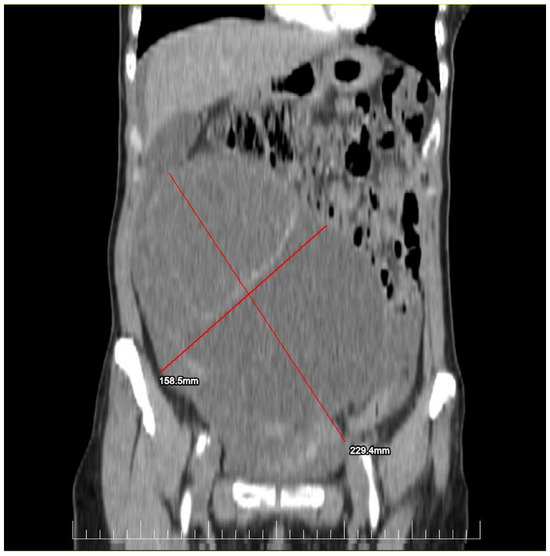

This case report details the presentation, diagnosis, and management of a 44-year-old female who experienced a relapse of colonic cancer with peritoneal carcinomatosis in 2021, two years after the initial diagnosis. The patient exhibited specific symptoms indicative of disease recurrence. In 2019, the patient underwent surgical resection and received adjuvant chemotherapy for colonic cancer. Despite an initial period of remission, in 2021 she presented with symptoms such as abdominal distension, persistent abdominal pain, and changes in bowel habits. Imaging studies, including CT scans, confirmed the presence of peritoneal carcinomatosis, indicating a relapse of colonic cancer along with two suspected tumorous formations localized in the ovaries (Figure 1 and Figure 2). Upon relapse, the patient underwent a thorough diagnostic workup, including imaging studies and tumor marker assessments. Elevated levels of carcinoembryonic antigen (CEA) of 5.44 ng/mL and CA-19-9 of 58 U/mL were observed, supporting the diagnosis of colonic cancer recurrence with peritoneal carcinomatosis.

Figure 2.

Preoperatory sagittal view of a CT image presenting a giant ovarian mass.